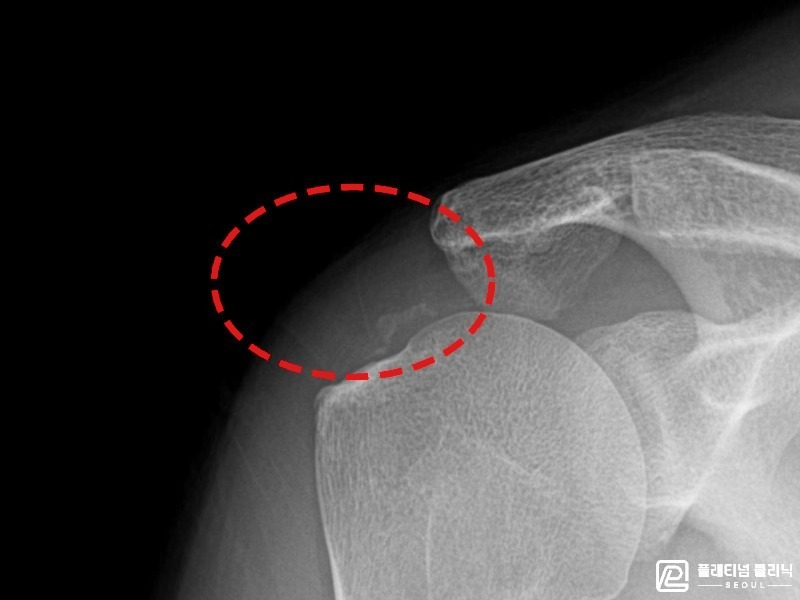

[촬영시기:21.11.15~21.12.02]

[석회분쇄흡입술] 우측 어깨 극심한 야간 통증으로 수면을 이루기 어려웠던 50대 여성 환자로, X-ray에서 극상근건 내 다량의 석회 침착이 확인되어 석회분쇄흡입술을 시행하였습니다.